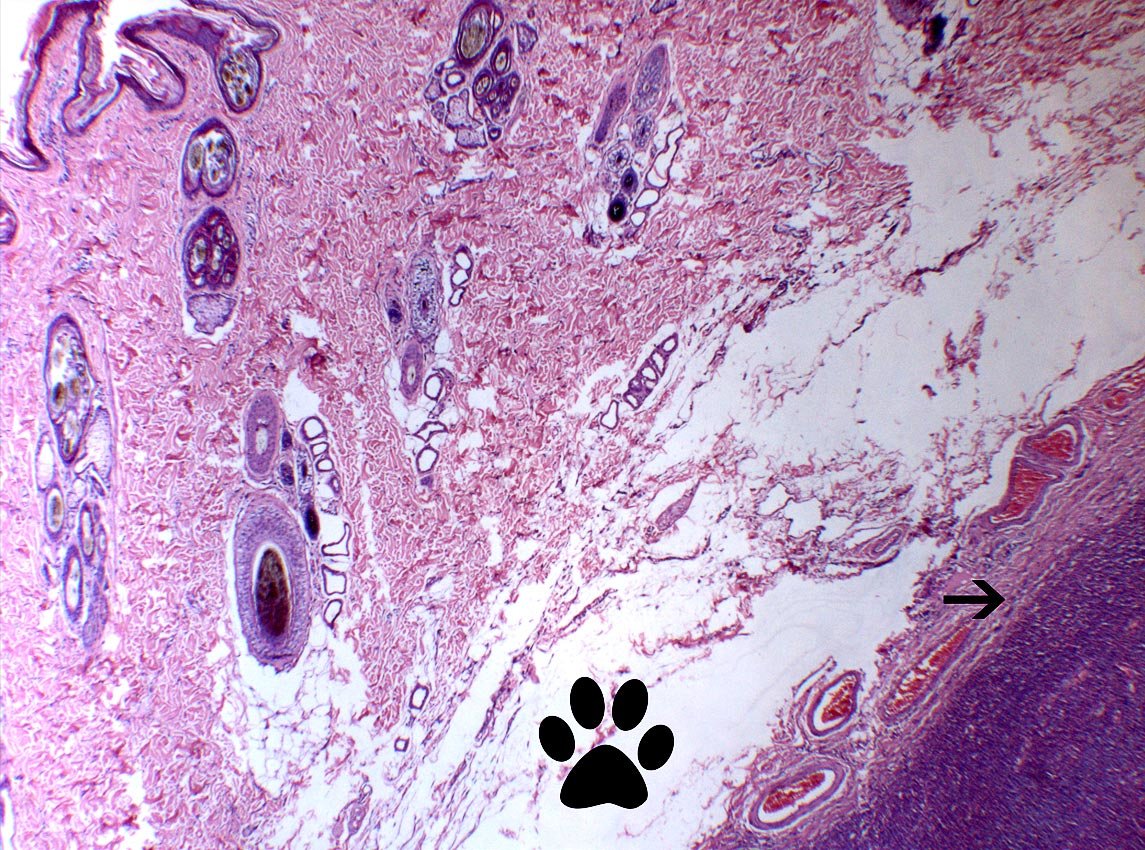

Concepto:En caninos, la mayoría de mastocitomas se origina de los mastocitos que se localizan en los diferentes estratos de la dermis(piel), expandiéndose posteriormente hacia el subcutis. Sin embargo, existen un grupo, el cual se origina mas profundamente,( tejido adiposo/ subcutis). De ahí el concepto deMASTOCITOMA SUBCUTÁNEO. Ver Fig. 2 A-B

Fig.2-A. La flecha superior indica la dermis profunda. La otra muestra tejido adiposo. Luego la masa(mastocitoma).

Caso contrario ocurre en la siguiente figura 3, en donde mastocitoma esta creciendo en la dermis, abarcándola de forma total.